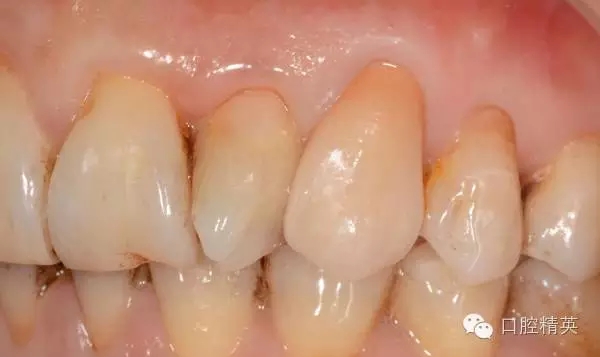

11.12.13頸部楔形缺損,探敏感,牙髓活力正常.

全口牙結(jié)石色素(+).

11.12.13 楔形缺損

二. 11.12.13.樹脂修復(fù)

三. 全口潔治